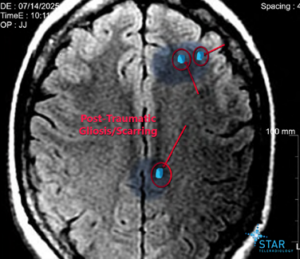

- A traumatic brain injury

Although she did not require surgery, her back remains her primary complaint and continues to require ongoing treatment. She has not yet returned to work as a CNA.